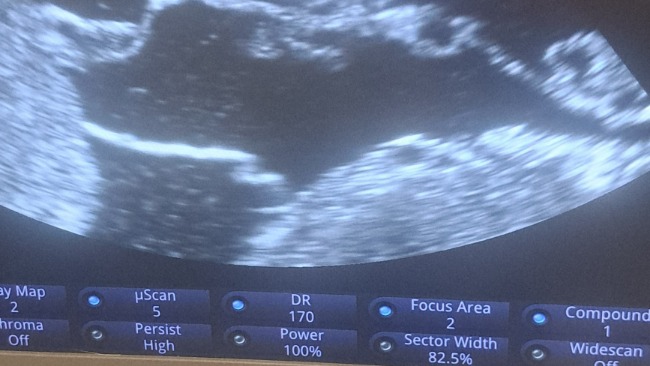

Ksenia od tygodnia zaczęła duzo pic i sikać. 4 czerwca zabrałam ją do lecznicy , usg wykazało płyn w jamie brzusznej . Została na noc w lecznicy , dzisiaj wysłany płyn z brzucha do badań, krew na PCR i inne badania .

P

owtórzylismy USG i okazało się ze nerki są w niepokojącym stanie .

Ze wstępnej diagnozy podejżenie zapalenia otrzewnej , dostała lek na ta chorobę i czekamy na wyniki .

Ksenia ma słabą odporność ponieważ jest nosicielem białaczki.